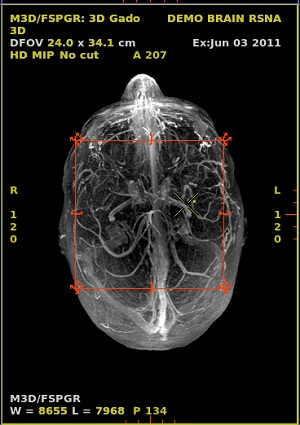

- To work in 3D, set the view type to 3D.

Figure 5. 3D image

- Right-click the rendering active annotation and select an option from the available modes. In Figure 6 example, right-click MIP.

Figure 6. 3D View